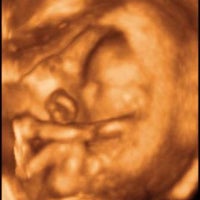

3D Ultrasound 4D Ultrasound Imaging Center For all of the expectant parents out there you can now see your unborn baby in live 4D motion with a 3D 4D or new HD ultrasound. We currently use the stunning 3D and 4D HD LIVE ultrasound allowing us to capture images of your baby provide gender determination and it also gives you a glimpse of how your little angel looks. Our High Definition GE Voluson E6 Ultrasound Machine Offers The Latest In State Of The Art Technology Which Gives Us And Our Excited Families Amazing Pictures Video.

We have spared no expense to create a 3D4D ultrasound facility that is unmatched in its class. With the 3D and 4D ultrasound images of your baby you will see your little angels movements like yawning stretching and you can even hear the babys heartbeat. My Sunshine Baby is dedicated to providing the very best expereince to pregnant mothers in the Charlotte NC area.

Witness the Miracle of Life with stunning 3D 4D and HD images of your little angel. Offering the NEWEST technology available in ultrasound imaging. Sweet Pea 3D is a 3D 4D Ultrasound Studio in Concord NC Charlotte Area.